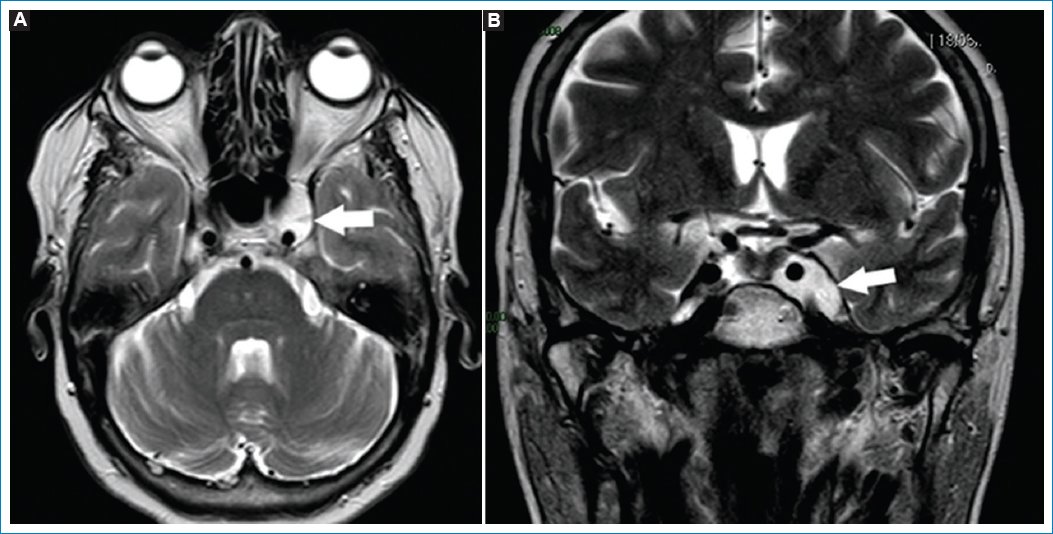

Figura 4. Imágenes potenciadas en T2. Corte axial (A) y coronal (B). Las flechas indican la presencia de meningocele cavernoso izquierdo. Este es valorado como un aumento del volumen del seno cavernoso afectado.

El quiste de Thornwaldt (QT) es una lesión benigna de la línea media de la nasofaringe, derivada de restos de la notocorda y el endodermo faríngeo21,22. Presenta una incidencia del 1,4-3,3%. Frecuentemente asintomáticos, pueden obstruir la vía aérea si crecen u ocasionar trastornos auditivos o dar síntomas si se infectan21,22. Suelen descubrirse en forma incidental mediante estudios por imágenes, realizados por otro motivo21.

La RM es el método de elección, apreciándose hiperintensos en T1 y T2, dado su rico contenido proteico, suelen no realzar con gadolinio (Fig. 5)21,22.

Figura 5. Quiste de Thornwaldt. Corte axial (A) y coronal (B), potenciados en T2. Las flechas señalan la presencia de una imagen de apariencia quística, hiperintensa en T2, en la pared posterior de la rinofaringe, compatible con QT.